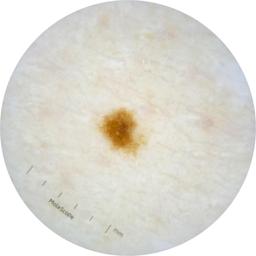

ISIC_2261268

acquisition_day 307

age_approx 50

anatom_site_1 Trunk

anatom_site_2 Posterior trunk

anatom_site_general posterior torso

concomitant_biopsy False

diagnosis_1 Benign

diagnosis_confirm_type single image expert consensus

family_hx_mm False

fitzpatrick_skin_type I

image_manipulation instrument only

image_type dermoscopic

lesion_id IL_8976478

patient_id IP_9156603

personal_hx_mm True

sex female